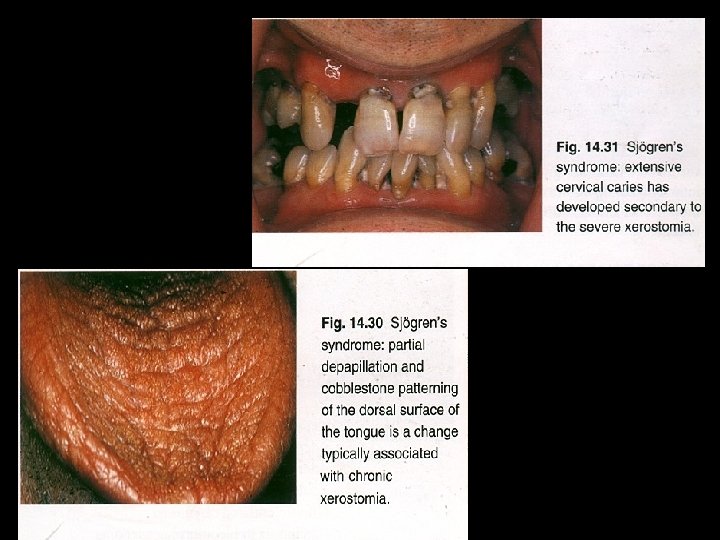

AUTOIMMUNE DISEASES: SJOGERNS SYNDROME HENRIK SJOGREN : 1933 CLINICAL TRIAD : Keratoconjunctivits sicca Xerostomia Rheumatoid arthritis

Primary Sjogren’s syndrome (Sicca complex) • Dry mouth and dry eyes Secondary Sjogren’s syndrome • Systemic lupus erythematosus, polyarteritis nodosa, polymyositis, scleroderma

C/F: • • • Usually in females over 40 yrs Children & young adults may be affected F: M– 10: 1 Dryness of eyes and mouth Painful, burning sensation of oral mucosa Lymphadenopathy is more common in primary form

Lab finding • Polyclonal hyperglobulinemia • Antisalivary duct antibodies, rheumatoid factor and antinuclear antibodies. • An increased sedimentation rate Radiography • formation of punctate cavity defect which are filled with radio-opaque contrast media • Cherry blossom or branchless fruit laden tree appearance

H/P • Intense lymphocytic infiltration of the gland replacing all acinar structures although the lobular architecture is preserved. • Proliferation of ductal epithelium and myoepithelium to form 'epimyoepithelial islands'. • An atrophy of the glands sequential to the lymphocytic infiltration.

XEROSTOMIA Clinical features : Dry mucosa Residual saliva : thick and ropey PT c/o diff in mastication & swallowing Diagnosis : Diseases : History Oral candidiasis radiation induced caries Clinical examination Investigations